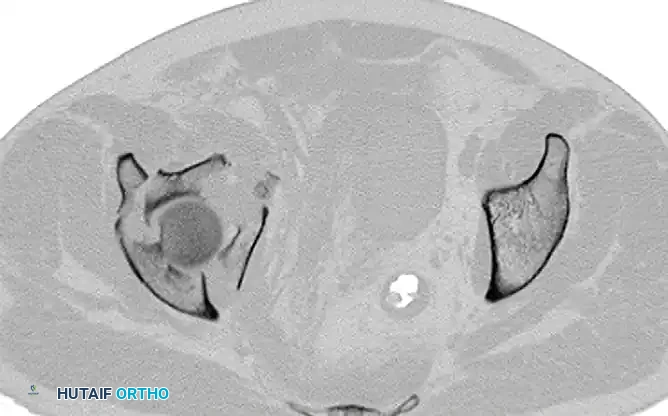

Both-Column Fractures and Indirect Reduction

Both-column fractures represent complete dissociation of the articular surface from the axial skeleton. These complex injuries often require extensive exposures or combined approaches. However, when treated through an ilioinguinal approach, indirect reduction techniques are frequently employed to restore the acetabular dome, with fixation placed on the internal surfaces of the pelvis to buttress the columns.

FIGURE 56-34: Both-column acetabular fracture treated through an ilioinguinal approach with indirect reduction of the acetabulum and fixation placed on the internal surfaces of the pelvis.